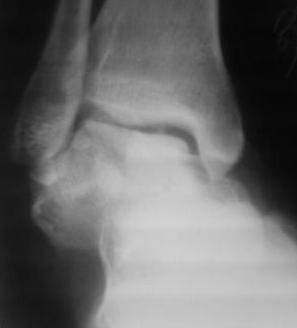

ya by popytalsya sobrat talus anatomichno,seichas pozdno operirovat iz za oteka,po etomy distrakziya apparatom budet optmalna.Posyalu vam podobyai moi sluchai.

14 years old girl

Fall from height ( 3rd floor)

Compressed fractures of L1-L2

Fx of orbital bone

Mark, судя по снимкам в день поступления произведен А.В.Ф., а остеосинтез ч-з какое время произведен?, остеосинтез произвели открытым способом?( на снимке п/о рубцы).

aparat postavlen v den postupleniya,rastaynuli, vpravili zakryto naskolko vozmoghno, a kogda otek spal sdelali otkrytoe vpravlenie.Teryat tut nechego, moghno tolko uluchshit.